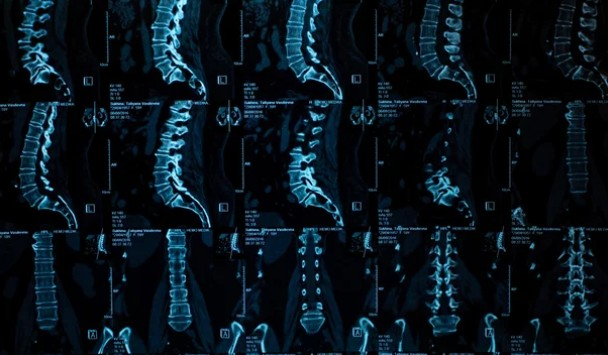

Patients suffering from sciatica, herniated discs, bulging discs, and chronic low back pain experienced not only dramatic pain reduction — but measurable anatomical changes confirmed through post-treatment MRI imaging.

- Disc height increased by 1.0–1.6 mm, reducing nerve root compression

- Spinal canal dimensions expanded by 1.5–2.1 mm

- Reduced intradiscal pressure promotes nutrient diffusion and disc rehydration

These findings strongly support the conclusion that spinal decompression does not simply “manage pain” — it actively improves the structural environment responsible for chronic nerve irritation.

But the most powerful findings were objective: post-treatment MRI scans revealed an average increase in disc height of 1.0-1.6 mm and spinal canal dimensions of 1.5-2.1 mm. This is not just temporary pain relief; it’s a physical, measurable change that addresses the root cause of the pain.

- MRI-verified improvements in disc height and spinal canal dimensions.